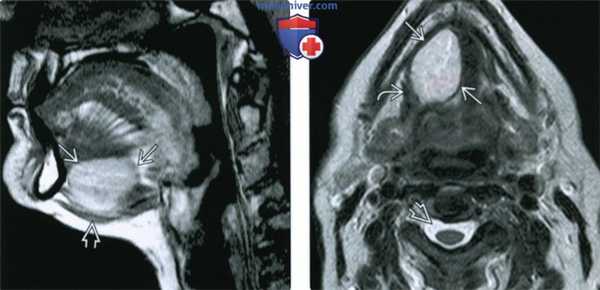

(Слева) На сагиттальной КТ (реконструкция) у десятилетнего ребенка с дермальным синусом носа определяется внутричерепное распространение дермоидной ки сты. Обратите внимание на кальцинат в области верхнего края дермоидной кисты.

(Справа) На сагиттальной томограмме (Т1 ВИ С+ FS) у ребенка в возрасте четырех дней с объемным образованием дна полости рта визуализируется патоморфологически подтвержденная многокамерная срединная дермоидная киста. В дифференциально-диагностический ряд нужно включать эпидермоидную кисту и лимфатическую мальформацию.

(Слева) МРТ Т1ВИ, сагиттальная проекция, эпидермоидная киста с гиперинтенсивным сигналом, происходящая из передних отделов корня языка и смещающая вниз мышцы дна полости рта. Гиперинтенсивный сигнал говорит в пользу высокого содержания белка.

(Справа) МРТ Т2ВИ, аксиальная проекция, тот же пациент. Неоднородный сигнал умеренно высокой интенсивности. Из-за высокого содержания белка сигнал гипоинтенсивный относительно ликвора. Вдоль латеральной границы образования проходит челюстно-подъязычная мышца.